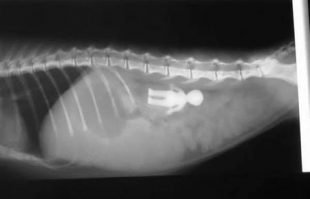

Psy sú veľkí jedoši a zjedia takmer čokoľvek ak na nich celé dni ako policajt nedozeráte. Čo všetko bizarné teda psy zožrali pri svojich "hladovkách"? Tento zjedol 19 tabletiek ukľudňovákov,.